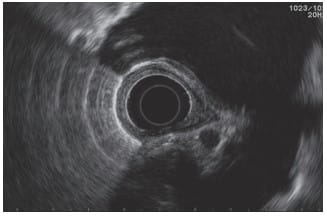

EUS offers a straightforward approach to evaluating the mediastinum. The images obtained by the radial scanning instrument in EUS correlate closely with those of CT scans, providing a high level of precision and detail.

Linear images in EUS, though more challenging to interpret, can yield significant insights when examined systematically. Mastery of this technique, particularly using a linear array echoendoscope, is crucial for a successful examination of the mediastinum.